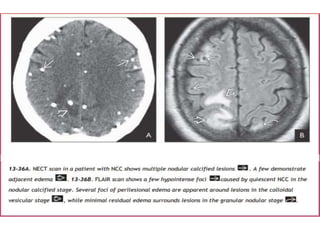

Granular nodular

• Odema decreases

• Cyst retracts

• Enhancement persists but is less marked

• NECT shows mild residual edema. CECT demonstrates an

involuting, mildly to moderately enhancing nodule.

• The cyst wall appears thickened and retracted, and the perilesional

edema diminishes substantially, eventually disappearing. Nodular or

faint ring-like enhancement is typical at this stage

Nodular calcified stage

• End-stage quiescent calcified cyst remnant

• No oedema

• No enhancement on CT

• Signal drop out on T2 and T2* sequences

• Some intrinsic high T1 signal may be present

• Long term enhancement may be evident on

MRI, and may predict ongoing seizures

Granular nodular • Odemadecreases • Cyst retracts • Enhancement persists but is less marked • NECT shows mild residual edema. CECT demonstrates an involuting, mildly to moderately enhancing nodule. • The cyst wall appears thickened and retracted, and the perilesional edema diminishes substantially, eventually disappearing. Nodular or faint ring-like enhancement is typical at this stage

Nodular calcified stage •End-stage quiescent calcified cyst remnant • No oedema • No enhancement on CT • Signal drop out on T2 and T2* sequences • Some intrinsic high T1 signal may be present • Long term enhancement may be evident on MRI, and may predict ongoing seizures